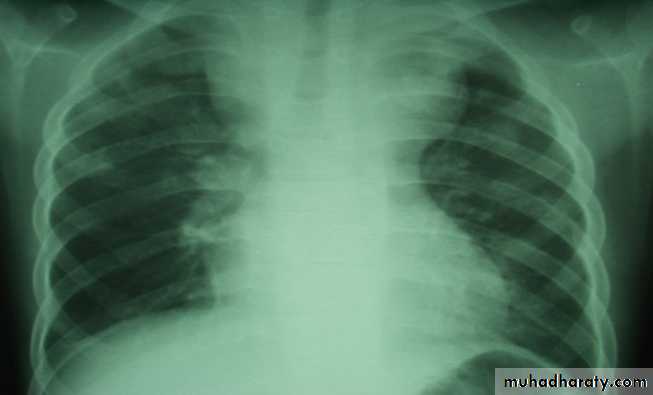

• 1.CXR, CBP & E.S.R, lymhocytosis• 2.Tuberculine -ve.

• 3.LN biopsy ( T.B Granuloma).